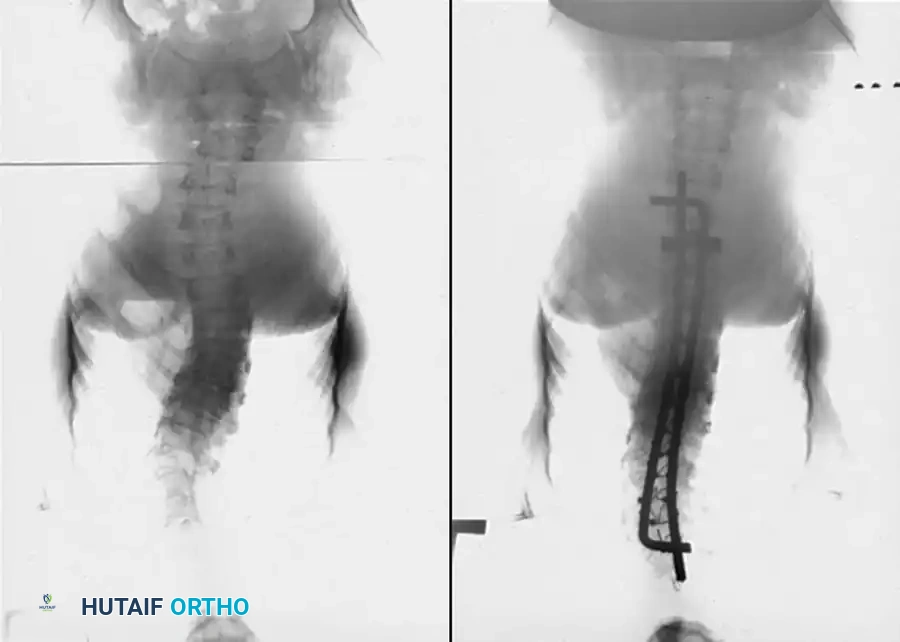

Fig. 38-216 A, Preoperative posteroanterior radiographs of a patient with osteogenesis imperfecta with progressing curvature. B, Postoperative radiographs after instrumentation with sublaminar cables and Luque rods.